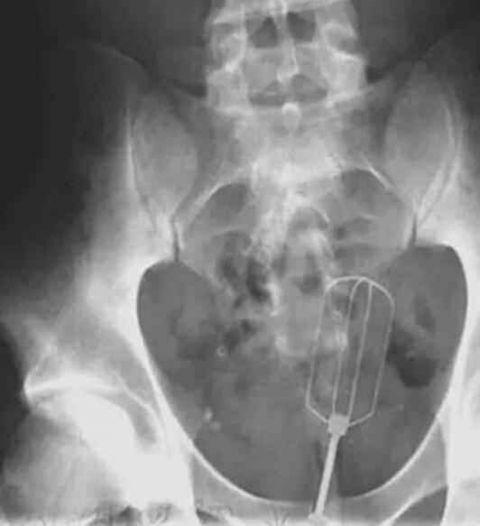

一把搅拌器